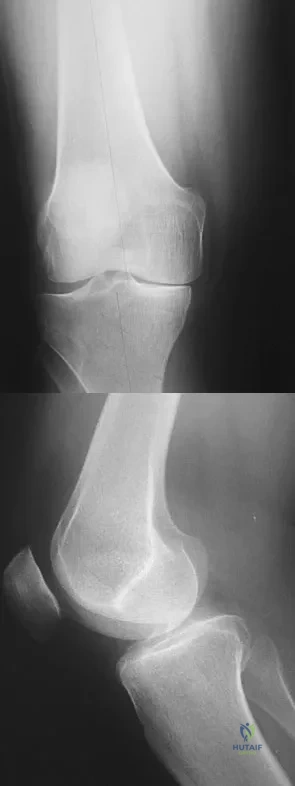

Question 55

A 38-year-old man who is an avid tennis player has had persistent pain over the medial aspect of his knee for the past 6 years. He notes that the pain occurs on a daily basis with any significant activity. Nonsteroidal anti-inflammatory drugs have failed to provide relief. Radiographs are shown in Figures 22a and 22b. What is the best course of action?

Explanation